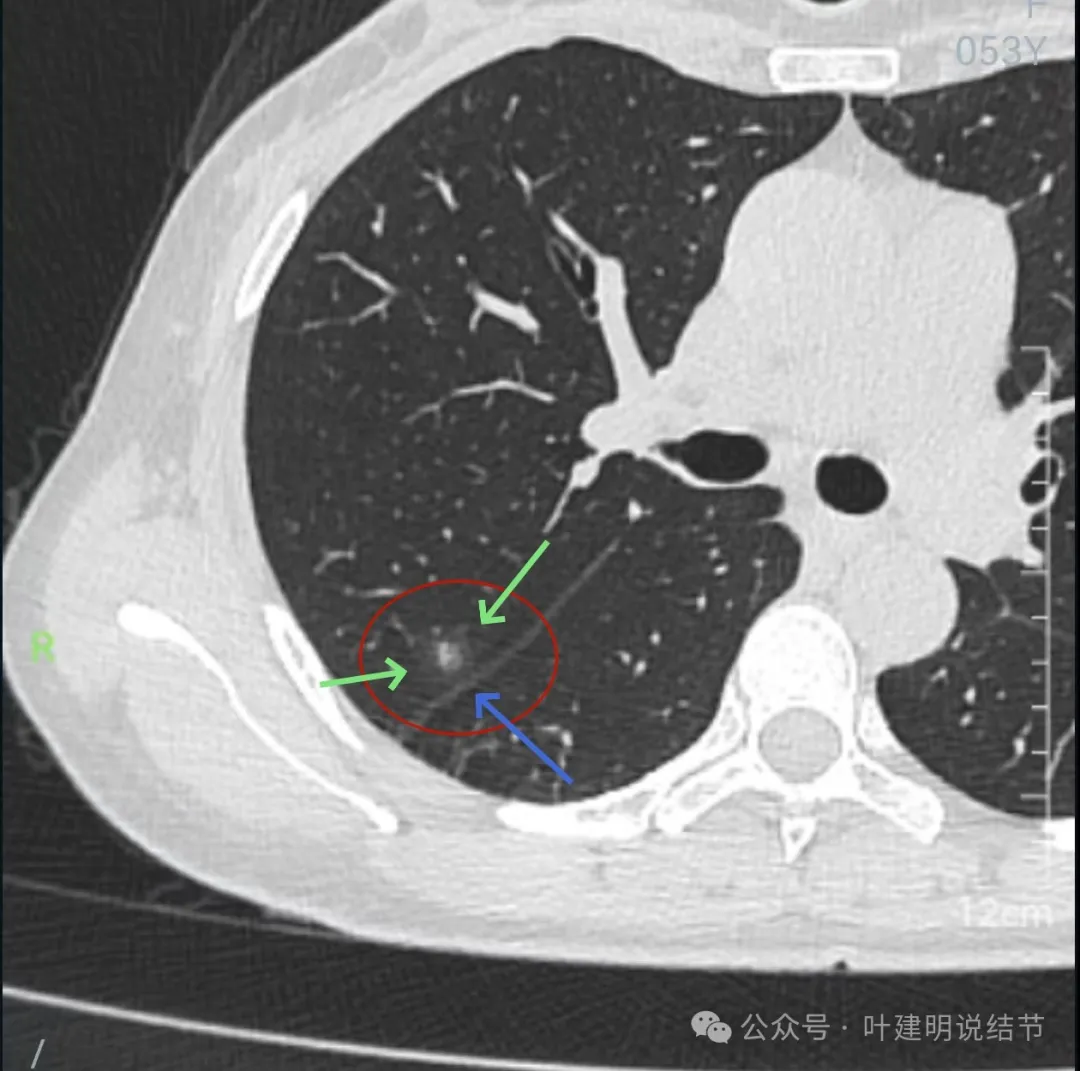

左下叶混合密度结节,边缘有淡的磨玻璃影,瘤肺边界欠清,实性成分明显,略偏散。

右下叶以及左下叶实性结节,缺乏膨胀性,没有收缩力,紧贴胸壁或膈肌无牵拉凹陷。

蓝色的是实性的小结节,缺乏膨胀性,两次检查都有,没有变化,考虑是良性的;红色的这些事10月份检查新增的,这两处比较明显的9月份的时候就是绿色框起来这个区域,当时是没有的。短时间内出现、多发病灶、边缘模糊、轮廓欠清,没有恶性特征,与炎性病变符合。建议查查隐球菌方面的化验,如此结果阳性,请呼吸内科或感染科处理。意见供参考!

再来看周教授认为4B类的右上后段病灶连续层面影像信息:

病灶出现,轮廓不清,瘤肺边界模糊,有血管穿行,血管有异常增粗。

血管壁有异常密度增高,病灶混合密度,轮廓总体在此层较清,但瘤肺边界不清。

病灶偏实性部分不密实,磨玻璃部分过淡且模糊。

边缘有毛刺,但不够锐利;外周磨玻璃成分密度过淡且界限不清;实性部分也显得不致密;与叶间裂距离近但没有任何牵拉影响。

实性成分在灶内看,也是界限不清,磨玻璃部分淡而糊。

整体感觉像病灶中间偏实性些的成分伴外周晕征。

边缘区域离叶间裂更近,仍无牵拉。

几乎贴着叶间裂了,仍无任何牵拉影响。

病灶密度边缘部分也不均,离叶间裂近而没有影响。

上图病灶已经贴着叶间裂,但仍显示是平直的,没有任何牵拉影响。

冠状位上看病灶有实性成分,实性成分缺乏收缩力,外围是淡磨玻璃成分,瘤肺边界欠清,贴着叶裂没有影响。

从连续层面以及影像细节上看,这个病灶就不可能是恶性的!短期内出现,混合密度而瘤肺边界不清,整体缺乏收缩力也无膨胀性,灶内实性成分不致密且磨玻璃成分过淡,灶内血管有异常增粗与密度过高,又是两肺多发病灶。这所有的表现与病情发展都与感染性病变契合,周围淡磨就是炎症水肿的关系,血管异常就是管壁有炎症的关系,多发就是感染(致病因素)影响两肺的关系。怎么可能是恶性?